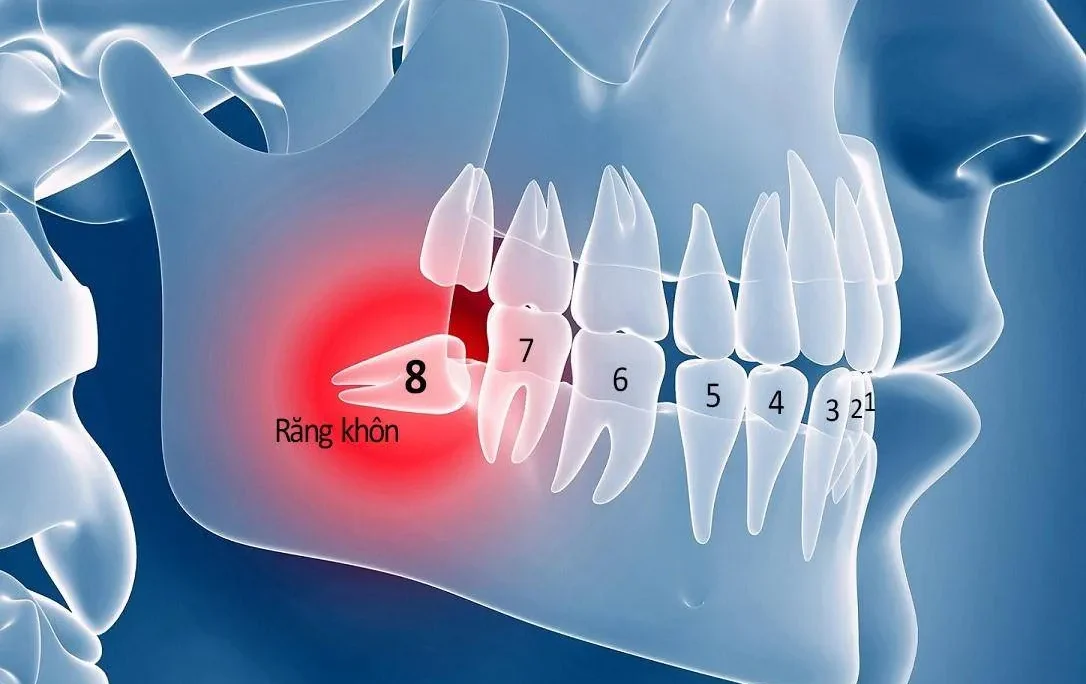

Lỗ sâu lớn thường xuất hiện phổ biến ở các răng hàm, đặc biệt là các răng cối. Điều này do vị trí của những chiếc răng này ở sâu trong khoang miệng. Từ đó khiến việc vệ sinh trở nên khó khăn. Hơn nữa, do các răng này thường không dễ quan sát. Theo thời gian các lỗ sâu nhỏ ban đầu có thể không được phát hiện ngay lập tức.

Khi tình trạng sâu răng trở nên nghiêm trọng, vi khuẩn có thể xâm nhập vào tủy răng. Từ đó gây viêm nhiễm lan rộng và làm tổn thương nghiêm trọng cấu trúc răng. Trong những trường hợp này, nếu không thể phục hồi răng, bác sĩ sẽ chỉ định nhổ răng. Điều này giúp ngăn ngừa lây lan của viêm nhiễm và tránh các biến chứng nguy hiểm.